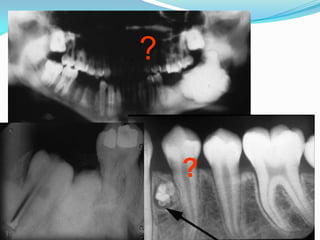

Radiographic findings

 Radiographs classically show a well-circumscribed,



expansile soap-bubble radiolucency with clearly

demarcated borders.

However, the unilocular lesion is indistinguishable from

an odontogenic cyst. The extent of root resorption may

indicate a neoplastic process.

Well-circumscribed, soap-bubble

Unilocular – often confused with odontogenic cysts

Root resorption – associated with malignancy

Odontoma: Radiographic Features

 Early lesions are radiolucent with smooth, well-

defined contours.

 Later a well-defined radiopaque appearance develops.

 The compound type shows apparent tooth shapes

while the complex type appears as a uniform opaque

mass with no apparent tooth shapes present.

?